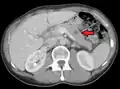

Metastases from the lungs to the pancreas

Metastases from the lungs to the pancreas